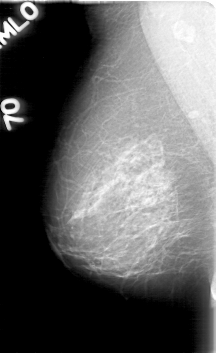

D_4019_1.RIGHT_MLO

RIGHT_MLO LINES 5281 PIXELS_PER_LINE 3226 BITS_PER_PIXEL 12 RESOLUTION 43.5 NON_OVERLAY